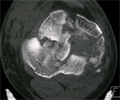

Pre

Op

CT Scan